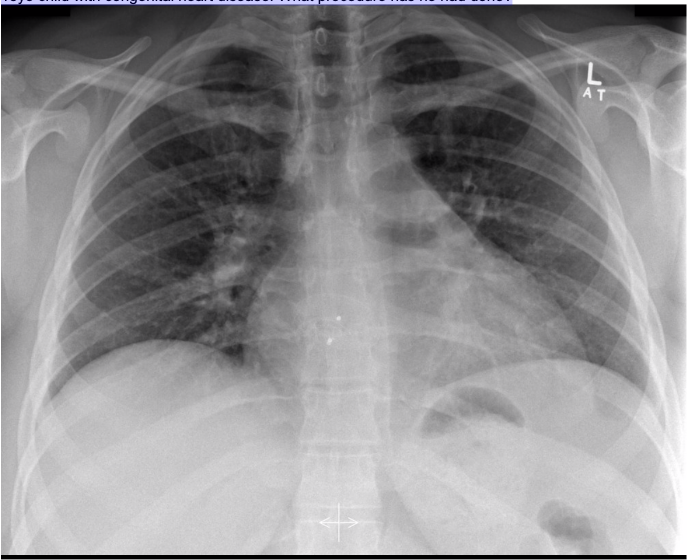

20.1 A 15-year-old boy undergoes a cardiac procedure for congenital heart disease. The intrathoracic device is a(n) (chest X-Ray shown)

c) ASD closure device

Amplatzer Device